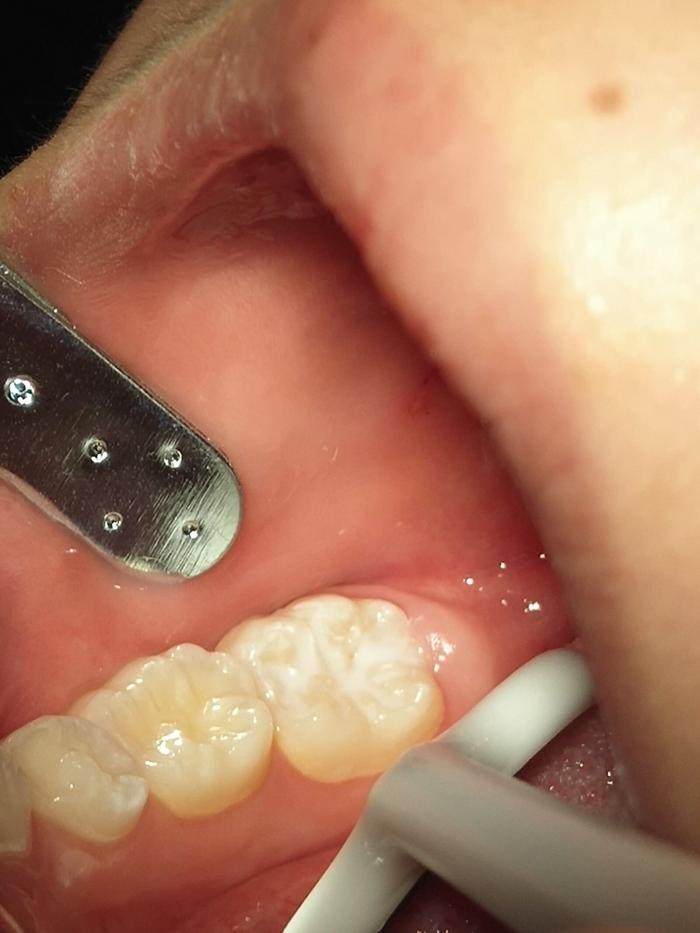

本网讯(通讯员 邓小瑛 李班)近日,在湘南学院附属医院口腔医院总能看到一道道亮丽的风景,一群群穿着校服的七、八岁儿童排着整齐的队伍有序来到口腔门诊,原来他们是来自郴州市各所小学二、三级的同学,集体预约来做窝沟封闭。

牙冠表面有些地方凹凸不平,凹陷处称为窝沟,窝沟不易清洁而且容易积聚菌斑,是龋齿的好发部位,而发生于窝沟的龋称为窝沟龋。

窝沟封闭对于“六龄牙”的保护尤为重要。六龄牙是6岁左右的宝宝在其乳牙的最后方长出的恒牙。这是人生中最为重要的牙齿,由于萌出时间早,使用时间长,再加上其牙齿上面有丰富的窝沟,极易发生龋齿。因此,对其的防护有着极其重要的意义。恒磨牙刚刚萌出1~2年内,是最易发生龋坏的时期,在此期间做窝沟封闭,越早效果越好。